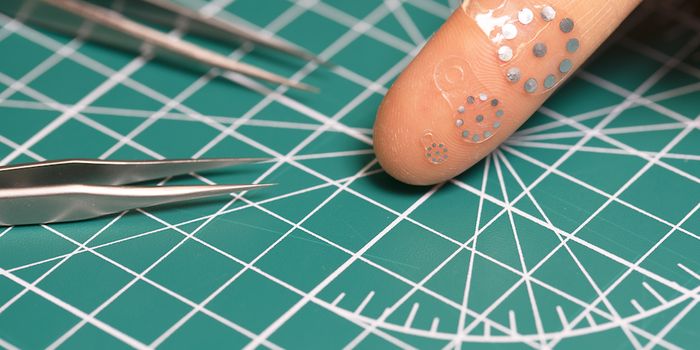

MAR 13, 2024Clinical & Molecular DXAfter gastrointestinal surgeries, patients are at serious risk of complications. But a cutting-edge device from Northwes ...